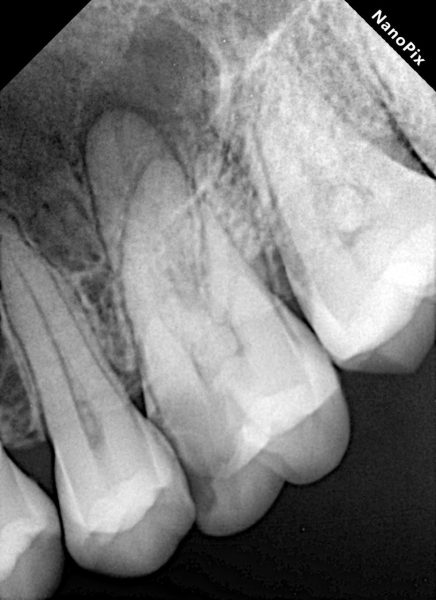

Need a clear and accurate diagnosis for your dental concerns? Our advanced tooth X-ray service in Karachi provides high-resolution digital imaging that helps detect cavities, infections, impacted teeth, bone loss, and hidden dental issues early and precisely.

Many dental issues develop beneath the surface and cannot be seen during a routine exam. Our state-of-the-art tooth X-ray services use high-definition digital radiography to accurately identify cavities, root infections, impacted teeth, periodontal bone loss, and other hidden oral conditions, allowing timely and effective treatment planning. At The Dental Clinic, we combine low-dose digital imaging with strict cross-infection control and international sterilization standards. Every dental radiograph is captured by experienced professionals to ensure optimal image clarity, minimal radiation exposure, and maximum patient safety.

Our advanced digital tooth X-rays deliver sharp, detailed images that help dentists identify problems early and plan treatments with confidence. Patients benefit from faster results and more accurate dental care decisions.

A tooth X-ray is a dental imaging technique that uses low radiation to capture detailed images of teeth, roots, and jawbone. It helps dentists identify cavities, infections, bone loss, and other issues not visible during a routine dental examination.

Dentists recommend tooth X-rays to detect hidden cavities, root infections, bone loss, impacted teeth, and other issues that are not visible during a routine oral examination.